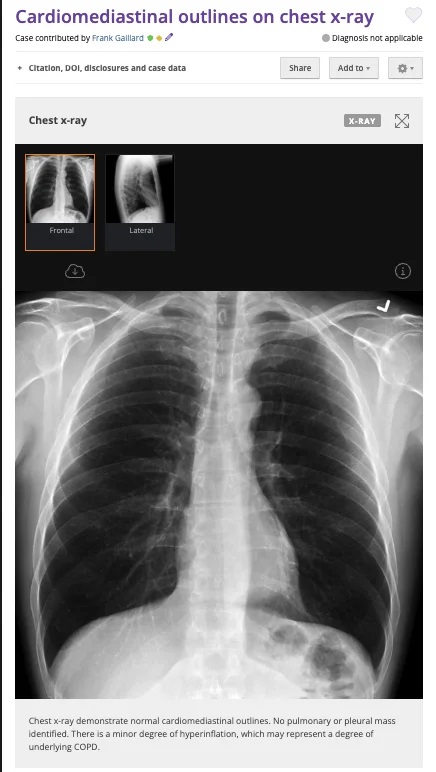

İddiaya eklenen fotoğraf tersine görsel arama yöntemiyle arandığında, “hamam böceğinin” fotoğrafa sonradan eklendiği anlaşılıyor. Fotoğrafın aslı standart bir göğüs röntgeni.

Orijinal görüntü 22 Ocak 2010’da bir radyoloji görüntüleri deposu olan “Radiopedia” üzerinden yayınlanmış.

- Fotoğraf, bir medikal arşiv sitesindeki göğüs röntgeni fotoğrafı manipüle edilerek oluşturuldu.